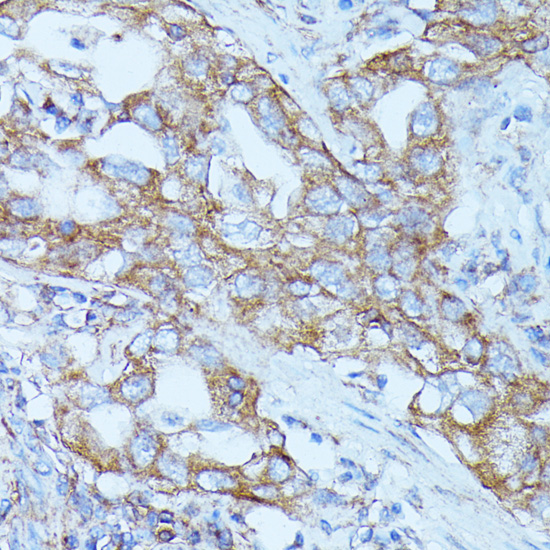

Immunohistochemistry of paraffin-embedded human lung cancer using FGD1 antibody.